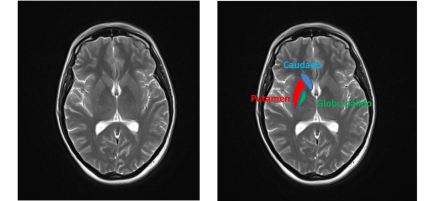

Continue reading →: DaTSCAN

El DaTscan o DaTSCAN es el nombre que recibe la prueba que consiste habitualmente en utilizar un radiofármaco llamado DaTSCAN o Ioflupano (123I) y posteriormente realizar una tomografía computerizada por emisión de fotón único (SPECT). El DaTSCAN está aprobado por la agencia europea del medicamento (EMA) en determinados casos para diferenciar los síndromes parkinsonianos…